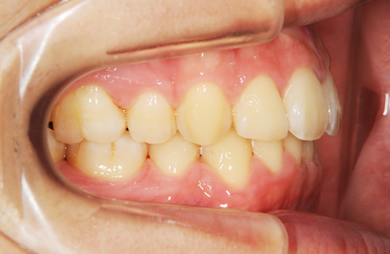

| 性別/年齢 | 男性 / 24歳 | ||||||||||||||||||||||||||||||||

| 主訴 | 乱ぐい歯を治したい。 | ||||||||||||||||||||||||||||||||

| 治療方針 | 歯のがたつきが大きいことより上下左右第一小臼歯を抜歯して、マルチブラケット装置にて治療。また、親不知がまっすぐ生えることができず横を向いている状態なので、まっすぐにする隙間があることから親不知も使用し、矯正を行う。 | ||||||||||||||||||||||||||||||||

| 治療内容 | 唇側矯正(ホワイト) | ||||||||||||||||||||||||||||||||